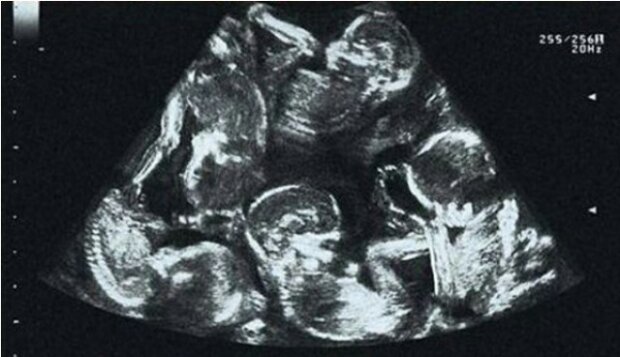

Takhle to začalo:

Alexandra Kiňová, když se dozvěděla, že je těhotná, byla z takové radostné zprávy neuvěřitelně šťastná. Těhotenství probíhalo dokonale, protože dívka byla mladá a zdravá. Saša se svou zajímavou polohou zacházela velmi opatrně a úzkostlivě, a když při prvním ultrazvuku zjistila, že má pod srdcem více než jedno dítě, na tuto zprávu klidně zareagovala.

Jak se ale ukázalo, před nimi se čekaly i další novinky. Když se termín prodloužil, lékaři zjistili, že žena bude mít čtyři děti! Ale i zde Alexandra projevila klid, nebála se, ale rozhodla se promyšleněji a pečlivěji připravit na nadcházející porod.

Dívka podstoupila všechna plánovaná vyšetření. A nějak se na jednom z těchto vyšetření ukázalo něco zcela neočekávaného! Lékaři napočítali už pět dětí. Dívka se neudržela a rozplakala se. Vůbec ne ze strachu, ale naopak ze štěstí. Koneckonců, ne každá žena je vybrána vesmírem pro takovou misi - pět dvojčat se narodí jen jednou za několik století.